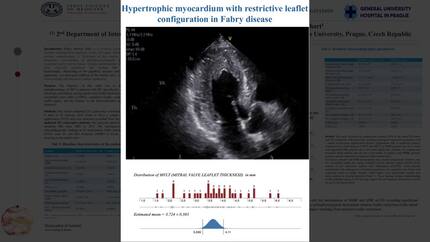

Doctor A. Vecerova (Prague, CZ)